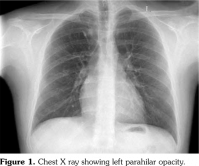

Chest X-ray showed left parahilar opacity (Figure 1). Pulmonary computed tomography (CT) angiogram revealed PAA with thrombus (Figure 2a). Bronchoscopy revealed no origin of bleeding. Echocardiography demonstrated mobile thrombus in the right ventricle (Figure 3a). Blood and urine cultures were sterile. Venereal Disease Research Laboratory test, tuberculosis tests, human immunodeficiency virus serology, antiphospholipid antibodies, anti-nuclear antibodies, and anti-neutrophil cytoplasmic antibodies were negative. Hereditary coagulation thrombophilic factors were normal.

The patient was treated with pulse steroid (intravenous methyl prednisolon 1 g/d for three days), intravenous cyclophosphamide (1 mg/kg/d), peroral azathioprine (125 mg/d) and peroral colchicine 0.5 mg/d. Peroral prednison was given after intravenous methyl prednisolon. Anticoagulation therapy was not administered. Patient was followed-up to one year. Reevaluation with pulmonary CT angiograms and echocardiograms demonstrated a remarkable regression of PAAs, and organization of intracardiac thrombus (Figures 2b and 3b, respectively). Currently, the patient is in a stable condition without hemoptysis or embolic event.